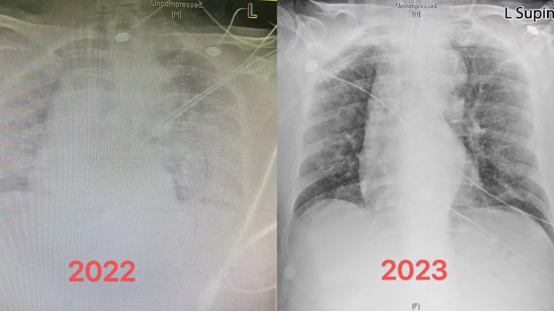

“您看,白肺并不可怕。经过规范治疗都会好转。咱们开始康复锻炼为脱(呼吸)机做准备!”重症医学科副主任赵慧颖举着两张胸片不断鼓励着兴奋地正在康复治疗中的刘奶奶。

刘奶奶被转到重症医学科时,胸闷、呼吸困难、血氧饱和度极低,严重缺氧,肺部影像呈现满满的白色状态,就是俗称的“白肺”。

重症医学科副主任赵慧颖解释道,“白肺”不是新冠病毒感染导致的症状,而是重症肺炎在X光检查下的表现。健康的肺是由通气功能正常的肺泡组成,这样的肺泡充满了空气,在 X 光和 CT 上都是透光的,并且显示为“黑色”。但如果肺部被炎症所广泛浸润,肺里的密度增高,透光性变差,这时在 X 光和 CT 上就表现为一种烟雾笼罩的“白色”。

刘奶奶肺部双侧病变90%以上,无法自主呼吸,氧饱和度不到70%,从急诊转到重症医学科后,立刻进行气管插管,保护性肺通气,并相应给予抗病毒治疗、低剂量激素抗炎治疗、循环管理等规范治疗,尽可能地保护器官储备功能,为患者恢复自身力量抵抗疾病争取时间。

“刘奶奶的康复,对于我们来说也是一种鼓舞,即使是这么严重的‘白肺’,在规范恰当的治疗下也是能康复的。以后会有越来越多的重症患者康复!”赵慧颖表示。